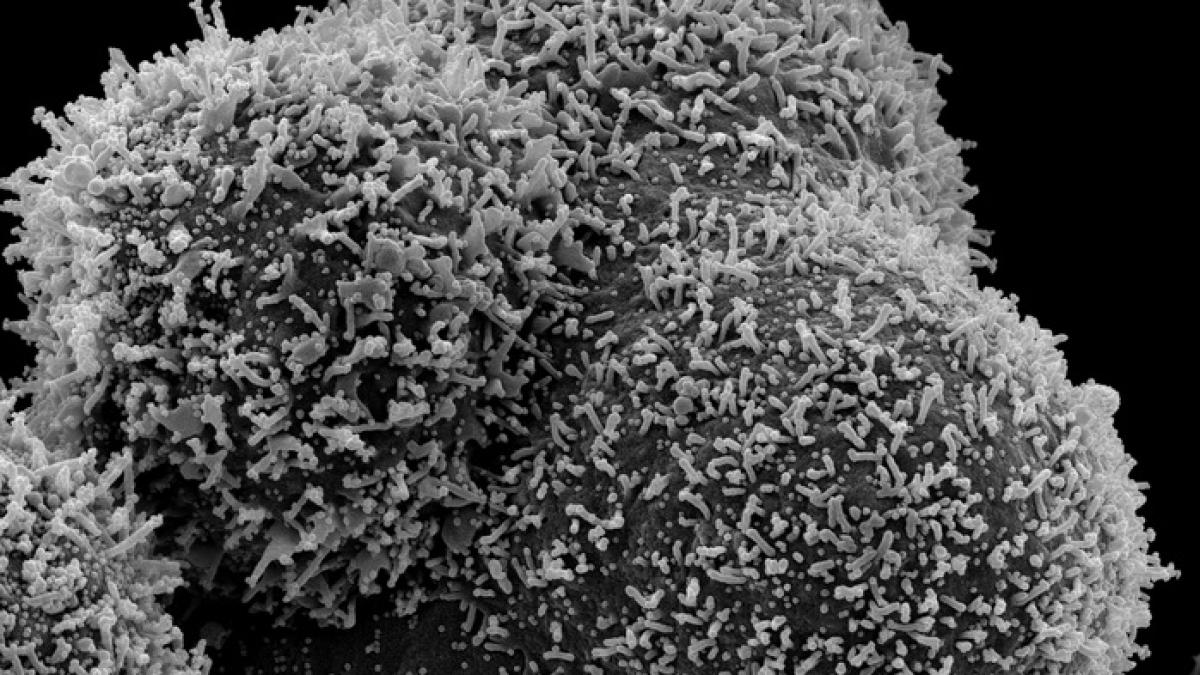

Ministrul britanic şi-a exprimat în ultimele săptămâni preocuparea cu privire la apariţia noilor tulpini, precum cele identificate în Africa de Sud şi Brazilia, în faţa temerii că actualele vaccinuri ar putea să nu fie la fel de eficiente pentru contracararea acestora.

"Ştiam că virusul va evolua de-a lungul timpului şi că unele mutaţii îl vor face potenţial să se răspândească mai repede şi ca oamenii să se contagieze mai rapid şi eventual să afecteze funcţionarea vaccinurilor", a precizat Isabel Oliver, care conduce Field Epidemiology Service (FES) din Marea Britanie.